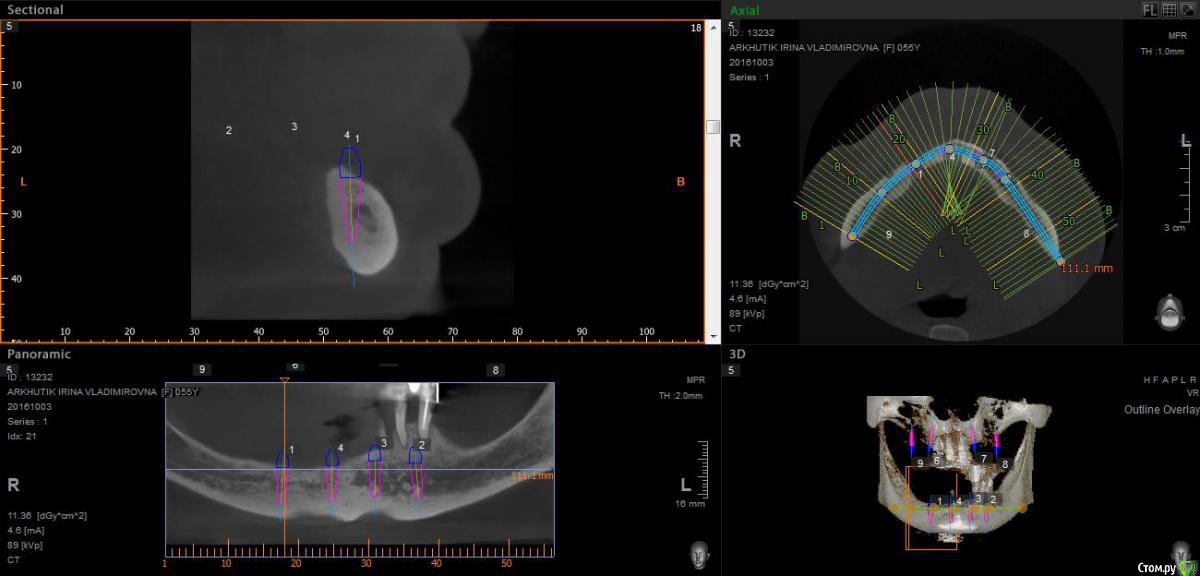

Rusty Опубликовано 5 октября, 2016 Поделиться Опубликовано 5 октября, 2016 Добрый день. К ортопеду обратилась пациентка 55-60 лет с такой ситуацией. Пришла с дочкой, дочь с мамой настаивали на несьемной конструкции, ортопед отправил на кт и вот. Не хочу планировать ей много хирургии, оцените и мой план пожалуйста и буду рад услышать советы по реабилитации пациента. По сути да) просто искал место куда есть возможность поставить, ортопед говорит тогда балка либо локаторы Ссылка на комментарий

Nazim_NV86 Опубликовано 5 октября, 2016 Поделиться Опубликовано 5 октября, 2016 На н/ч балка? Какие измерения в дист отделах? На в/ч мало четырёх. По три бы. Ссылка на комментарий

Rusty Опубликовано 5 октября, 2016 Автор Поделиться Опубликовано 5 октября, 2016 На н/ч балка? Какие измерения в дист отделах? На в/ч мало четырёх. По три бы.На н/ч балка, в дистальных отделах над каналом около 3мм. На вч условий для установки больше 4 не нашел) Ссылка на комментарий

Nazim_NV86 Опубликовано 6 октября, 2016 Поделиться Опубликовано 6 октября, 2016 Попробуйте на вч поискать ещё возможность хотя бы по Палаччи поставить. Ссылка на комментарий